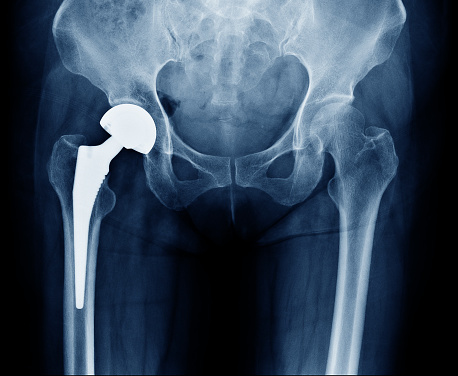

Your doctor may decide to just remove the femoral head from the body and replace it with a prosthetic metal head. Because only half of the joint has been changed in this condition, this procedure is called hemi arthroplasty .Sometimes orthopedists have to replace both the femoral head and the acetabular cavity (Complete hip replacement); This type of surgery is called total arthroplasty. Therefore, total hip arthroplasty is a type of orthopedic surgery in which the hip joint is Completely replaced with an artificial joint.

In this type of surgery, the femoral head is removed and a metal artificial head is inserted instead.

The inner surface of the acetabular cavity is removed and replaced with a metal bowl covered with a layer of polyethylene. The metal head is placed inside this metal bowl and thus the whole hip or hip joint is replaced with an artificial joint.